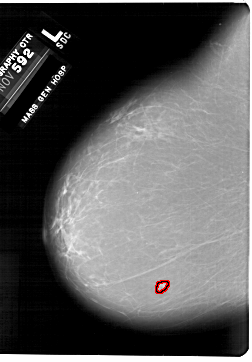

A_1876_1.LEFT_CC

LEFT_CC LINES 6871 PIXELS_PER_LINE 4771 BITS_PER_PIXEL 12 RESOLUTION 43.5 OVERLAY

FILE: A_1876_1.LEFT_CC.OVERLAY

TOTAL_ABNORMALITIES 1

ABNORMALITY 1

LESION_TYPE MASS SHAPE LOBULATED MARGINS MICROLOBULATED

ASSESSMENT 4

SUBTLETY 3

PATHOLOGY BENIGN

TOTAL_OUTLINES 1

BOUNDARY